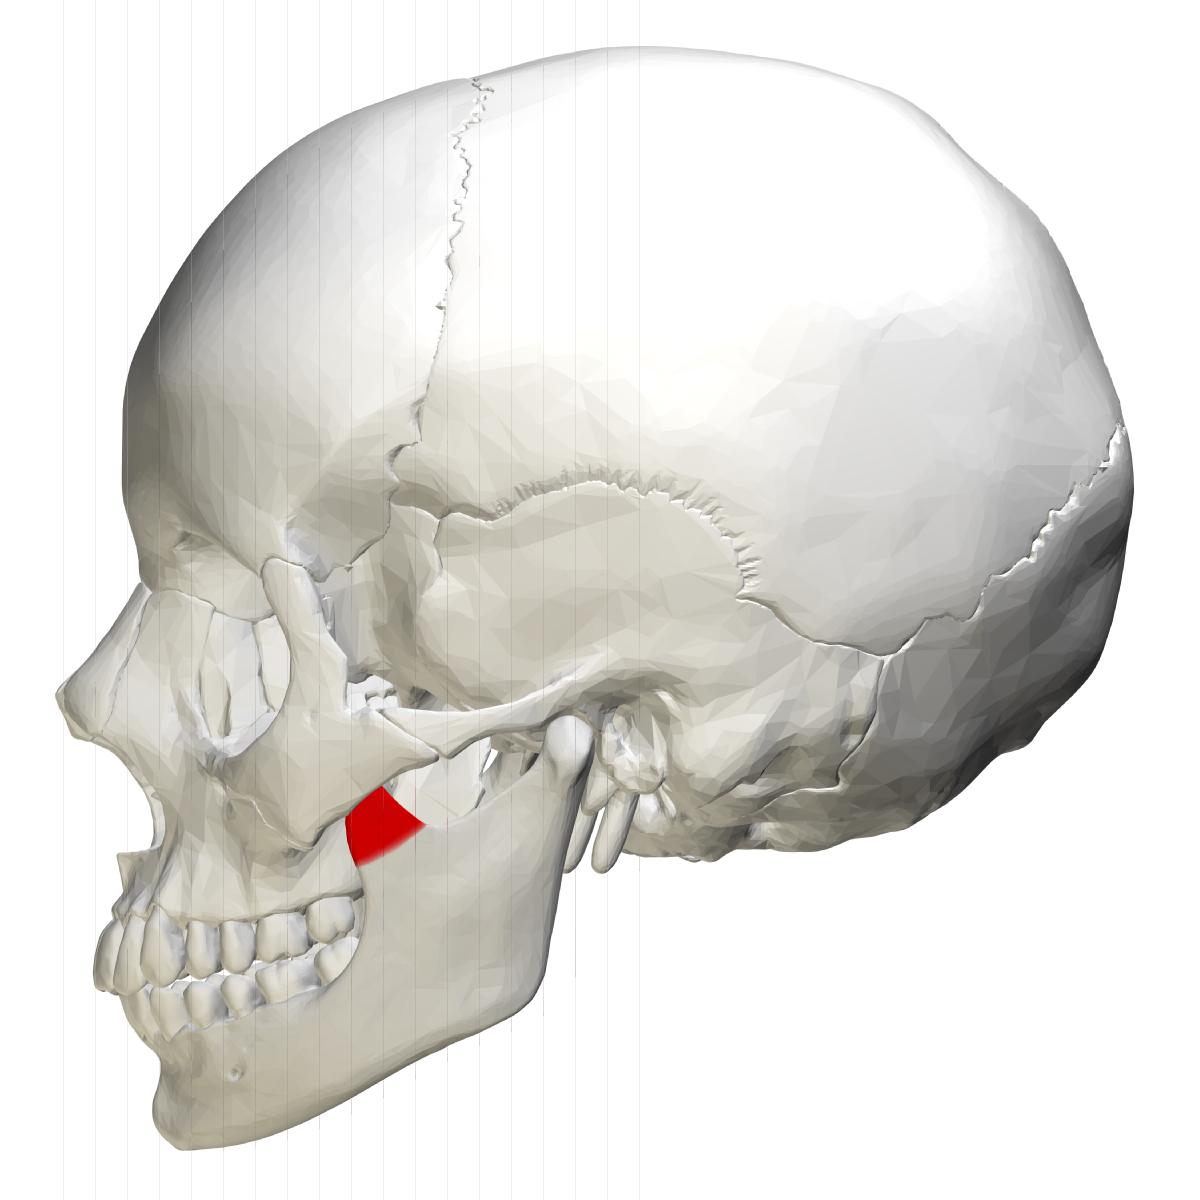

what is this, its description and its appearance on images- 1st line

lingula

small tongue shaped projection seen adjacent to mandibular foramen

radiopacity, not seen intraoral